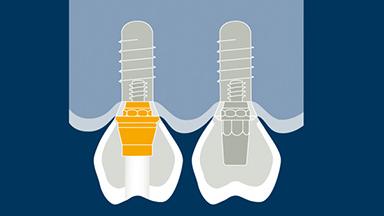

The first point is selection of the type and configuration of the FDP. The next point is selection of the retention method, followed by consideration of the external aspects and internal structure required to address factors such as esthetics, function, and strength.

- selection of retention method